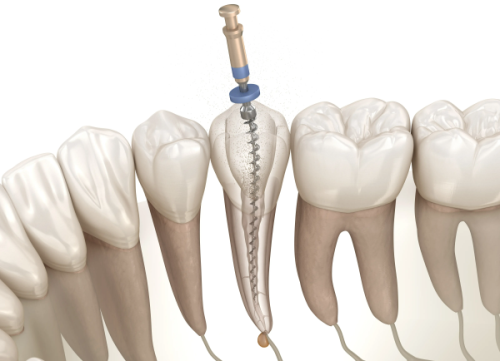

综合治疗项目

| 上颌智齿拔除 | 159 - 299元起 |

| 牙周治疗 | 根据病情与方案定价 |